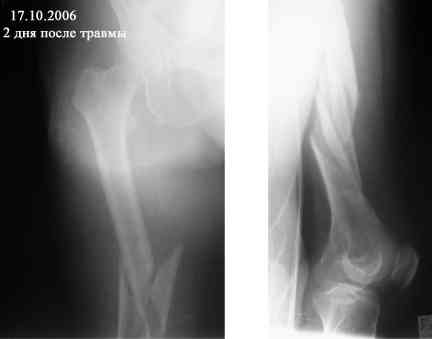

Представляю вашему вниманию снимки в динамике